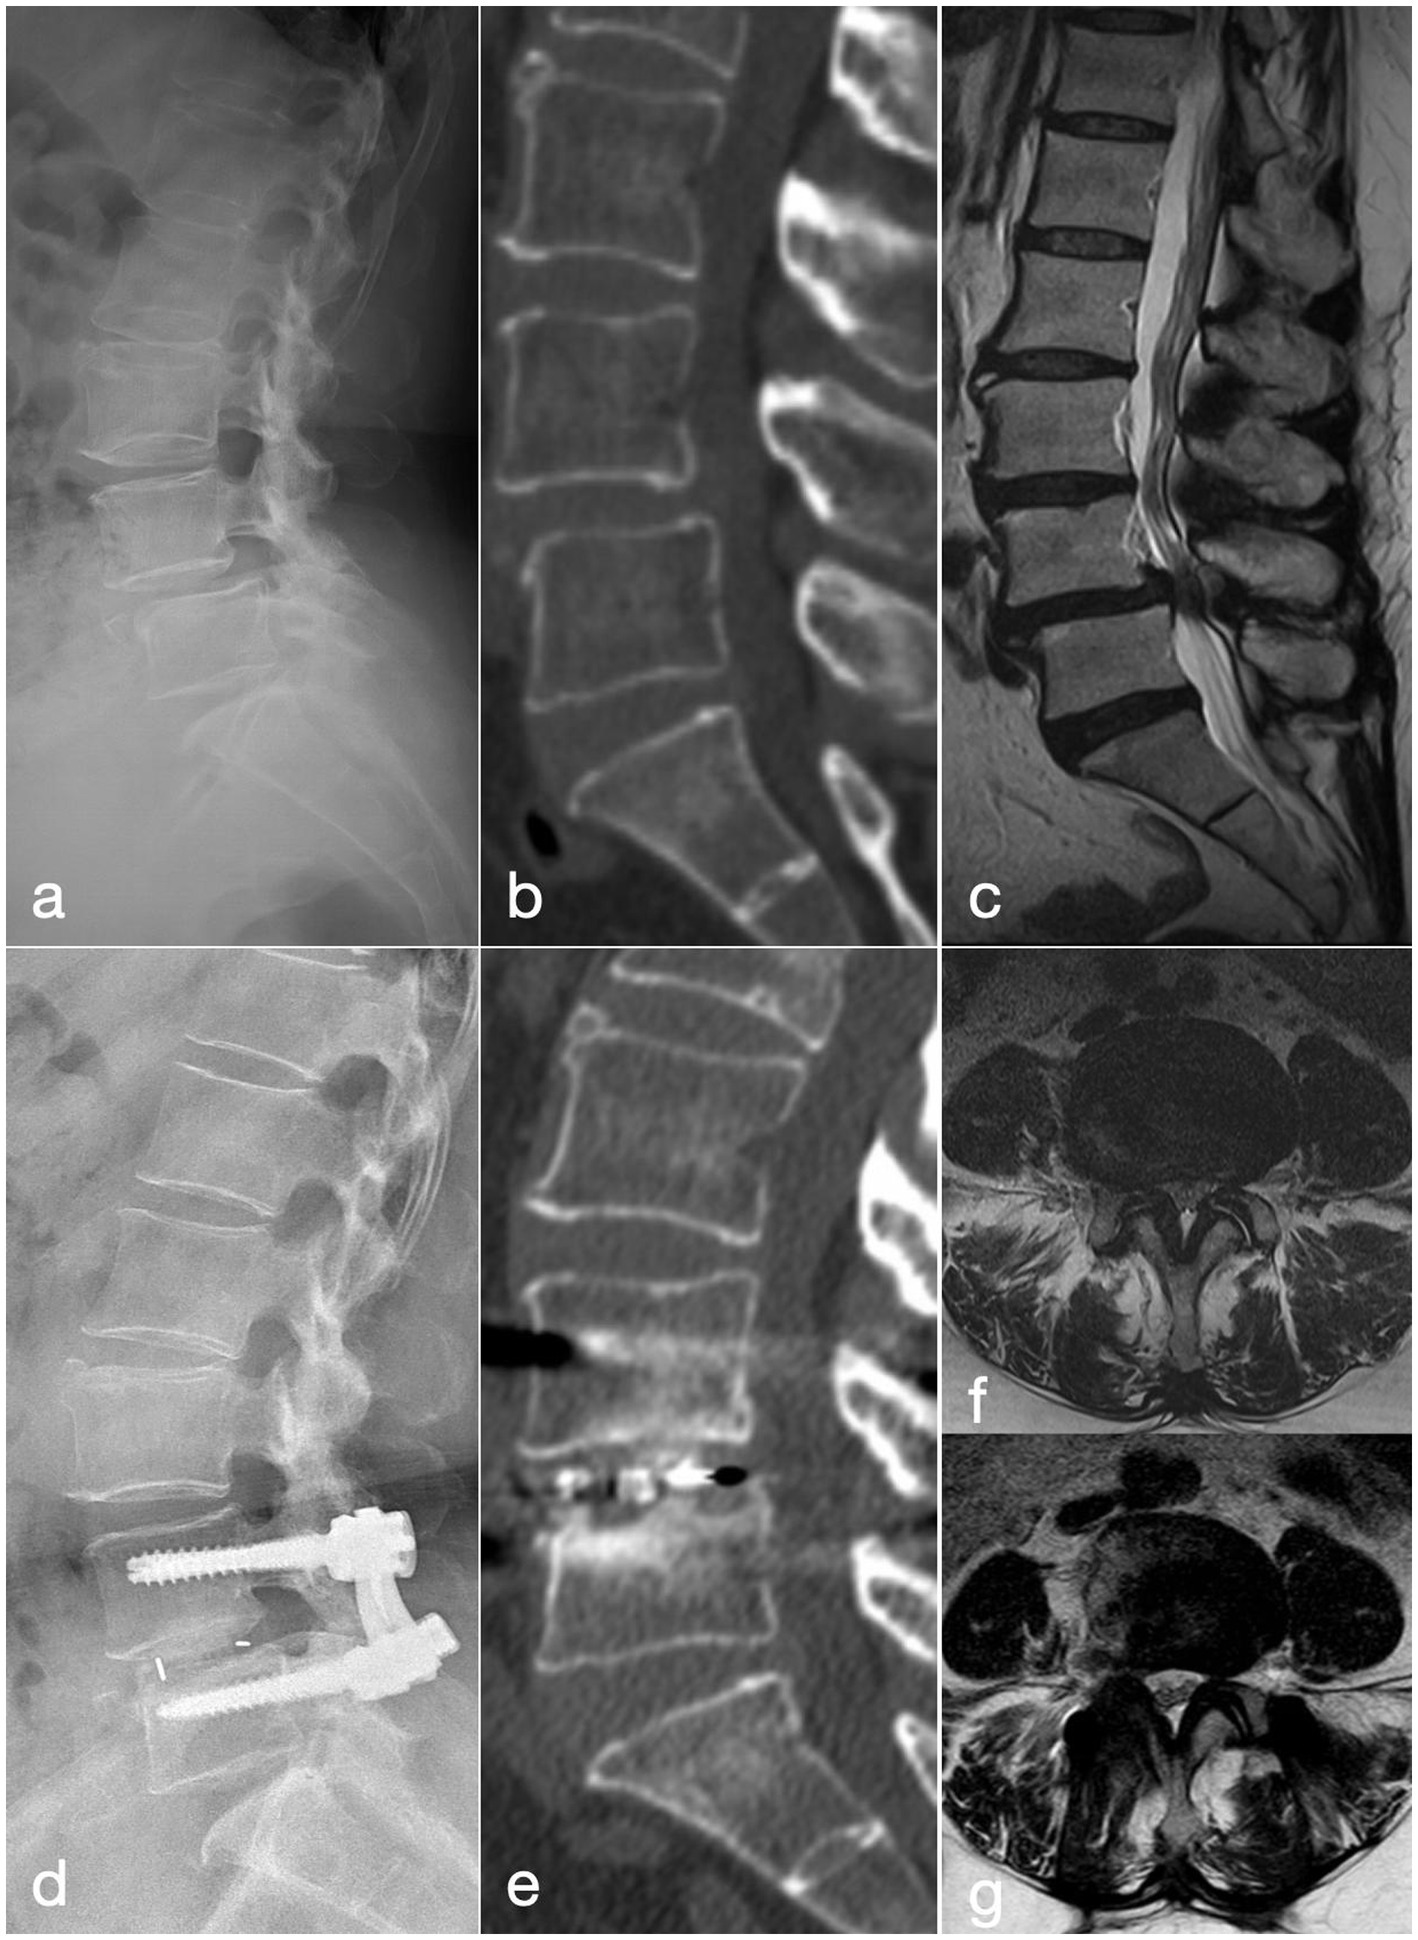

Figure 2

A 57-year-old woman with recurrent low back pain and lower limb intermittent claudication of 9 months’ duration, was treated with the MIS-TLIF procedure. (a–c) Pre-operative lateral radiograph, CT and MRI show grade-I anterior spondylolisthesis of L4. (d) Post-operative lateral radiograph demonstrates well-positioned instrumentation and interbody cage with good reduction of the slip. (e) CT at 2 years confirms solid interbody fusion at L4/5. (f) Pre-operative MRI reveals severe L4/5 central canal stenosis. (g) MRI at 2 years shows increased canal volume and patent cerebrospinal fluid signal.